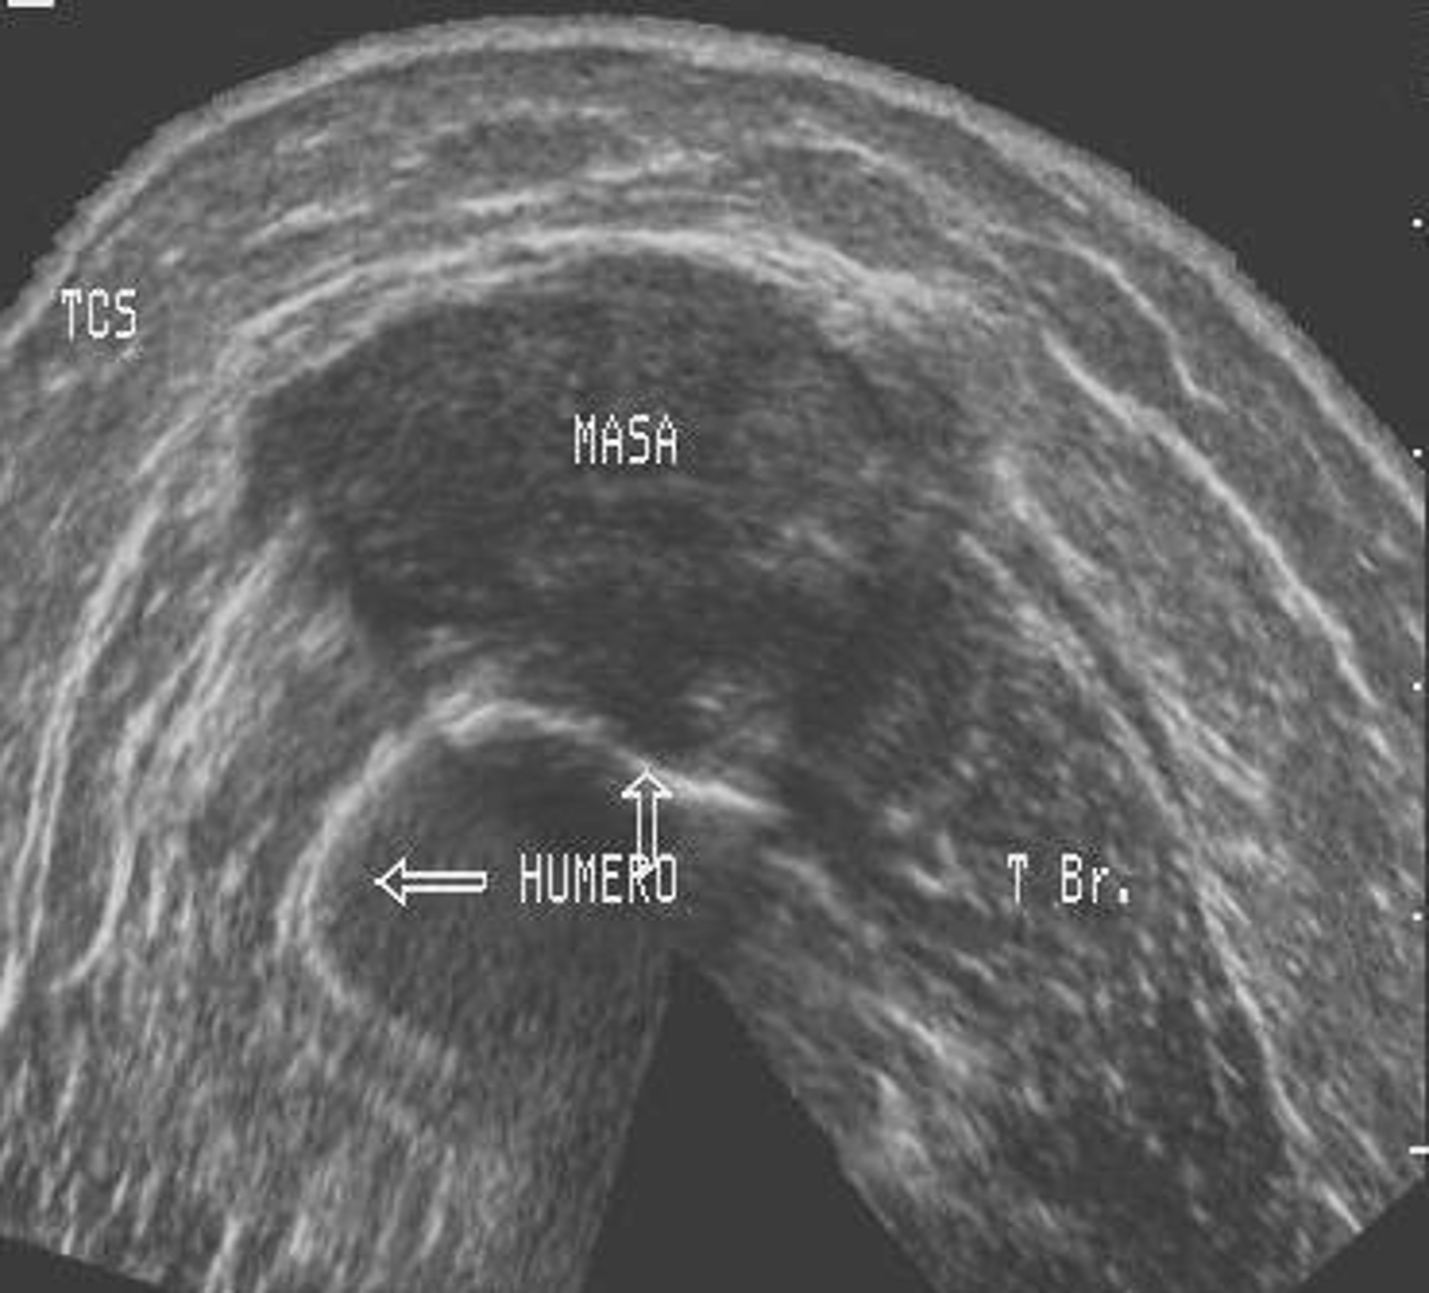

Interpretación especializada del sistema osteomioarticular

Nos enfocamos en la interpretación de ecografías de , tendones, músculos y articulaciones, lo que nos permite detectar con precisión cualquier anomalía o lesión en estas áreas.